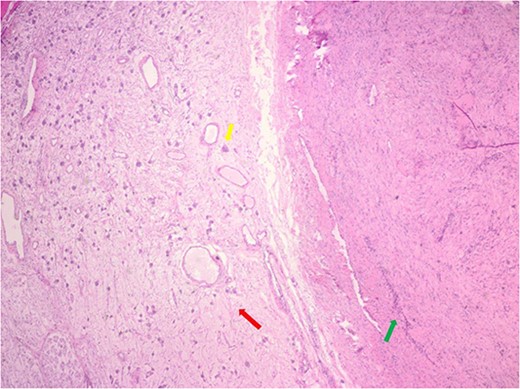

The pathology demonstrated an Ancient Schwannoma (see Fig. 3) with an adjacent ganglioneuroma (see Fig. 4). Because of the benign nature of this tumor, no further workup was required.

Hematoxylin and eosin stain pathologic slide of ancient schwannoma (green arrow) and adjacent ganglioneuroma (red arrow) with ganglion cell (yellow arrow).